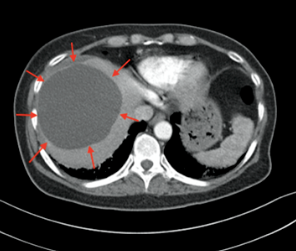

B型超声检查诊断肝囊肿具有敏感性高、无创伤、简便易行等优点,<1cm的囊肿也易检出,准确率达98%,而且能确定囊肿的性质、部位、大小、数目及累及肝脏的范围,为本病的首选检查方法。典型的超声表现是,肝脏上显示的圆形或椭圆形无回声区,部分在囊内可出现分隔;若有囊内出血、感染等,囊液可有高回声的光点,甚至在囊内可发现气泡,这时需结合患者临床症状综合判断。鉴别诊断是排除多囊肝、肝包虫病、肝脏黏液性囊腺瘤等。

还有一些患者肝脏内囊肿的数量非常多,或是合并脾脏或肾脏内也有多发的囊肿,就需要警惕先天性多囊肝、多囊肾、多囊脾的情况,这类囊肿会随着年龄的增大而增大,但进展非常缓慢,可能后期才会出现肝功能、肾功能的异常。

多囊肝最常发生于多囊肾患者。在多囊肾患者中,肝囊肿的发病率随年龄的增加而增加,年龄小于30岁时约为10%,年龄大于60岁时则超过50%。这些看似来源于胆道上皮的囊肿更常见于晚期肾脏疾病患者。